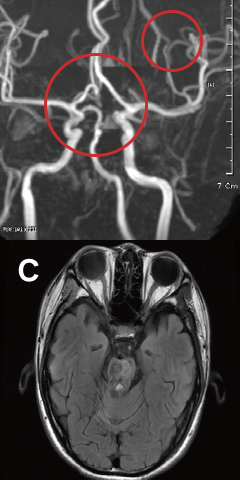

뇌졸중

Stroke-

발병시

-

줄기세포 치료 15일 후

줄기세포 치료 41일 후

끊어진 뇌혈관 주변으로 새로운 혈관이 형성 되었습니다.